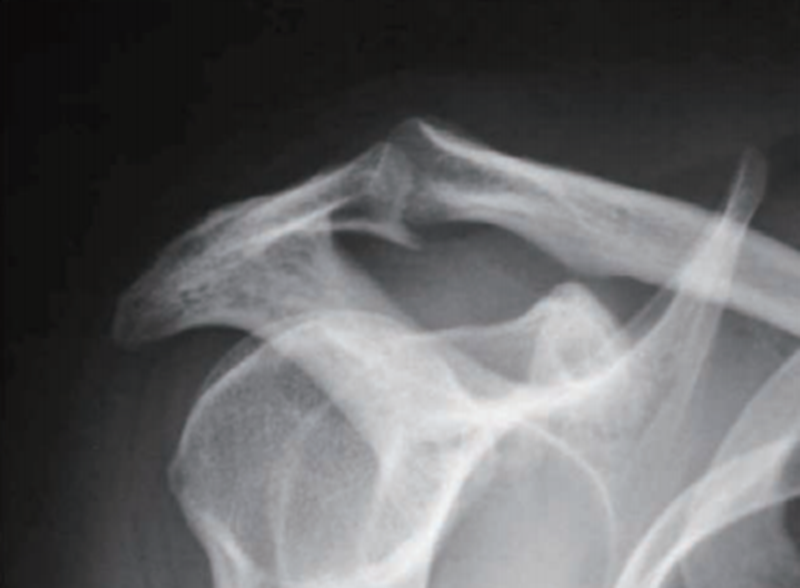

有学者认为肩峰的增生、硬化以及骨赘的形成是肩袖损伤后的继发性改变。因此,如果在慢性患者冈上肌出口位X线片上观察到明显的肩峰下骨赘,或者弧形及钩形肩峰,是肩袖损伤的有力提示(图4)。

图4 肩峰下骨赘X线影像